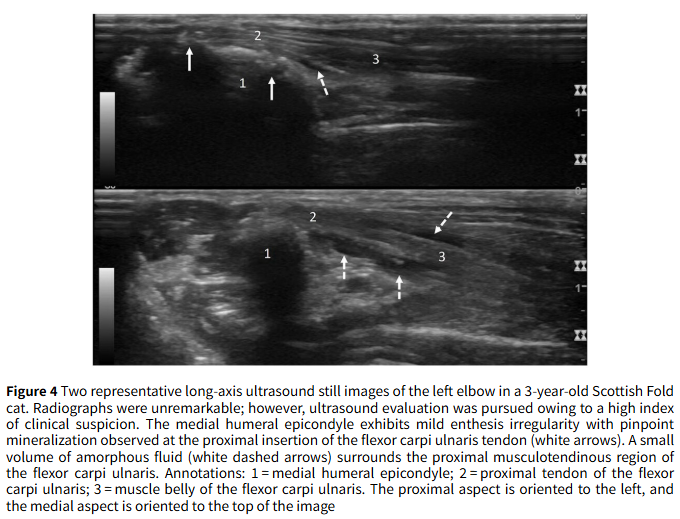

- 결과 2: 영상 진단의 유용성 방사선 검사만으로는 질병의 전체적인 상태를 파악하기 어려웠습니다. CT 촬영을 진행한 10개의 팔꿈치 중 7개에서 방사선으로는 확인되지 않았던 추가적인 문제, 특히 **관절 내 유리체(mineralized bodies)**가 5개의 팔꿈치에서 발견되었습니다. 또한, 방사선 소견이 경미했던 4개의 팔꿈치에 대해 초음파 검사를 시행한 결과, 힘줄 주변의 미세한 염증과 초기 단계의 광물 침착을 발견할 수 있어 조기 진단에 대한 초음파의 가능성을 확인했습니다.